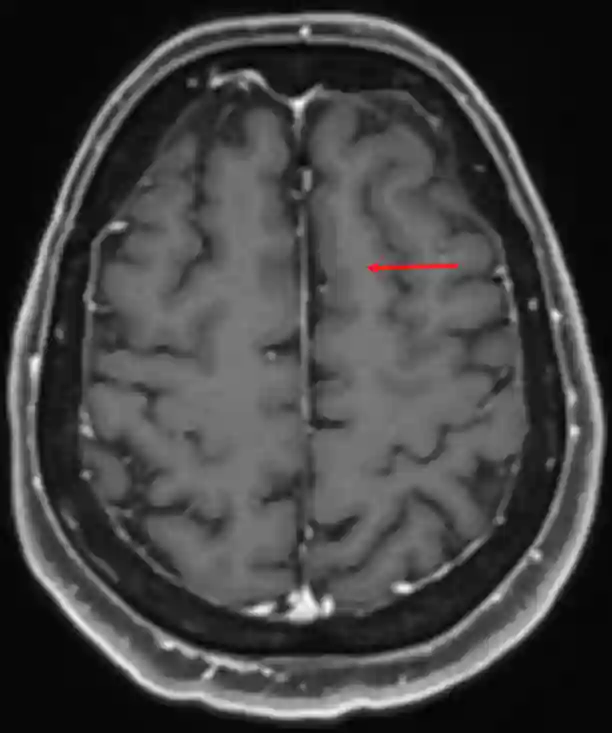

Gyrus frontalis superior im MRI

Gyrus frontalis superior in der axialen Ebene in einer T1 Kontrastmittel Sequenz im MRI.

Gyrus frontalis superior im MRI.